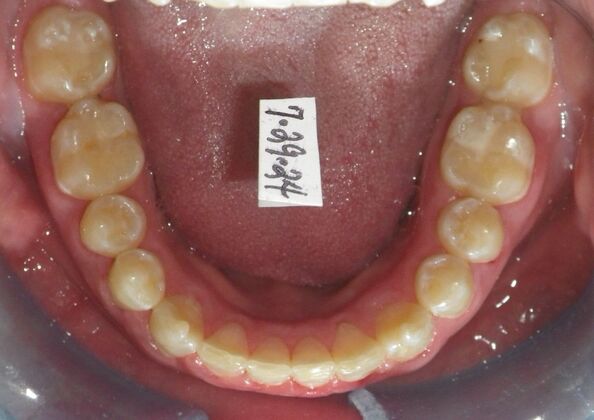

Orthodontic treatment in Phases: Case 12

This patient does not like his anterior deep bite and the flaring of the right lateral incisor as well as anterior spacing. The solution was to correct his Class II molar relationship, Division II and deep anterior bite and close spacing as much as possible with addition of composite restorations on distals of lateral incisors. We began with utility archwires, eventually correcting Class II molar with distalizing appliance, and continued with final tip and torque. All that is left now is to ad composite to distals of upper lateral incisors.